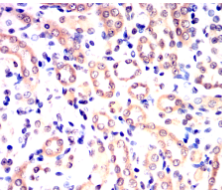

IHC    1/200 - 1/1000